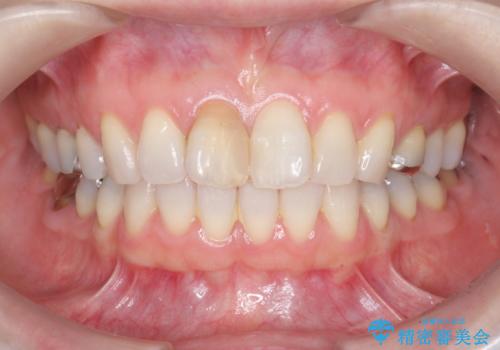

前歯の変色 セラミック審美補綴

このような場合、セラミックによる審美改善が治療の一案として提案されます。